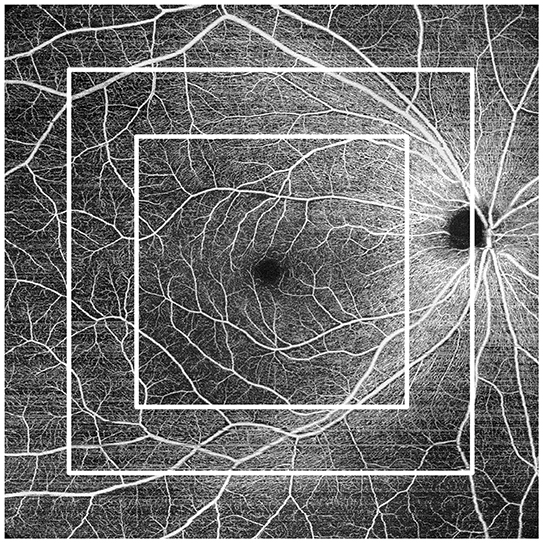

Enhanced OCT-A resolution with a new imaging algorithm

Sharp, wide OCT-Angiography enables detailed imaging of microvasculature even at the periphery of the scan area. In addition, a new algorithm, Complex OCT signal Difference Analysis Angiography 2 (CODAA 2), improves contrast, allowing for enhanced imaging. The high-definition OCT-Angiography enables greater clinical use of noninvasive imaging of retinal vascular diseases, reducing dependence on contrast dye tests.